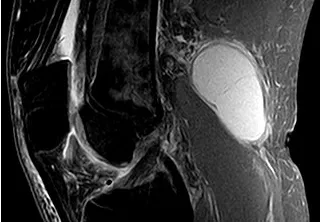

Resonancia magnética (RM): Puede proporcionar una imagen detallada de la estructura de la rodilla y ayudar a identificar cualquier problema subyacente en la articulación.